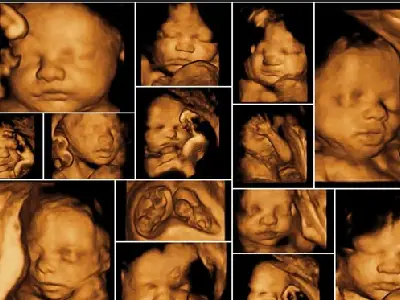

The anomaly scan is a comprehensive ultrasound that provides detailed images of the developing baby. A trained sonographer carefully examines several aspects of fetal development during this scan.

Anomaly Scan Ultrasound During Pregnancy

Detailed Examination: The ultrasound checks the baby’s head, brain, face, spine, heart, lungs, stomach, kidneys, limbs, and other organs to ensure they are forming properly.